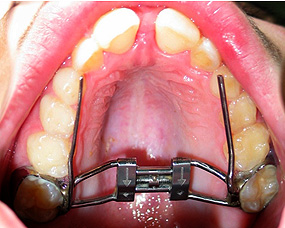

O tratamento ortodôntico nas crianças, com dentição decídua (dentes de leite), é muito importante para corrigir ou redirecionar o crescimento ósseo dos maxilares, permitindo a correta erupção dos dentes da dentição definitiva e uma melhor oclusão (engrenamento dentário).

![]() |

A disjunção maxilar e a expansão alveolar na criança, são dois bons exemplos, de como a Ortodontia pode intervir para tratar ou minorar um problema, que mais tarde seria bem mais difícil de resolver de forma não cirúrgica. Neste caso, a função corretiva e preventiva do aparelho dentário, contribui igualmente para a diminuição do tempo de um previsível tratamento ortodôntico futuro, quando terminada a erupção da dentição definitiva.